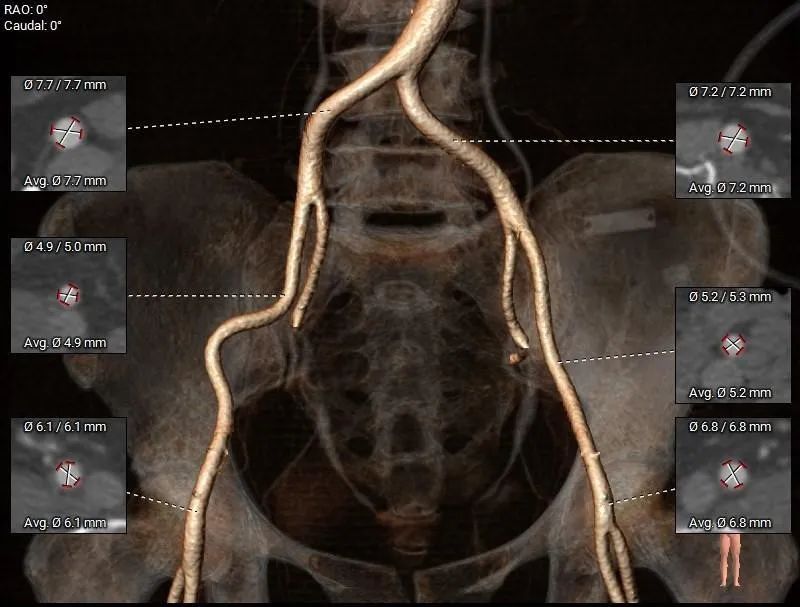

外周入路

股-髂动脉走行可,内径可,无钙化分布

• 股-髂动脉走行可,内径可,无钙化分布,建议入路穿刺规范操作,硬导丝有效支撑下小心通过,避免血管损伤及相关并发症。